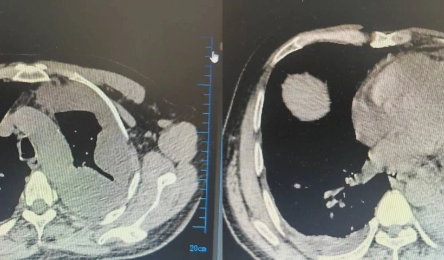

• “心”征程 再启程!我院胸痛中心通过国家再认证

日前,国家胸痛中心2025年第一批次再认证结果公布,我院胸痛中心凭借卓越的综合实力、高效的救治体系和优质的医疗服务,顺利通过复审。       国家胸痛中心认证体系以“严苛、规范、高标准”著...